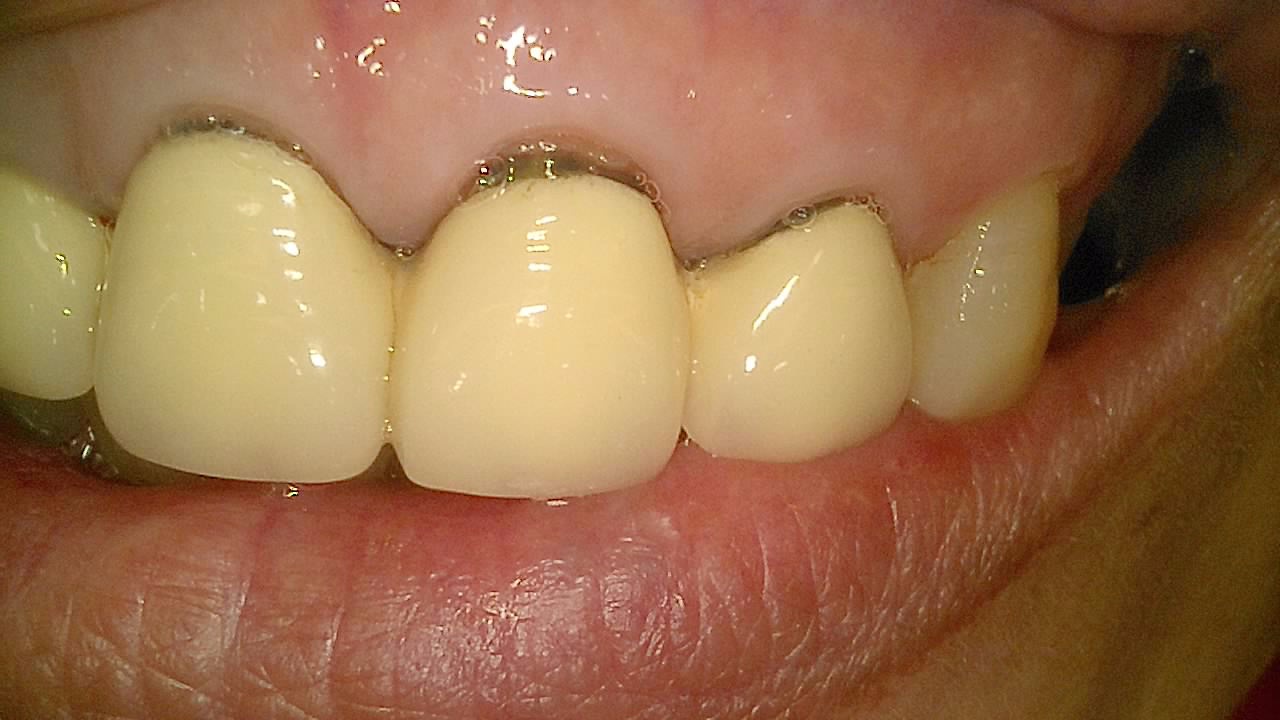

임플란트

BEFORE & AFTER